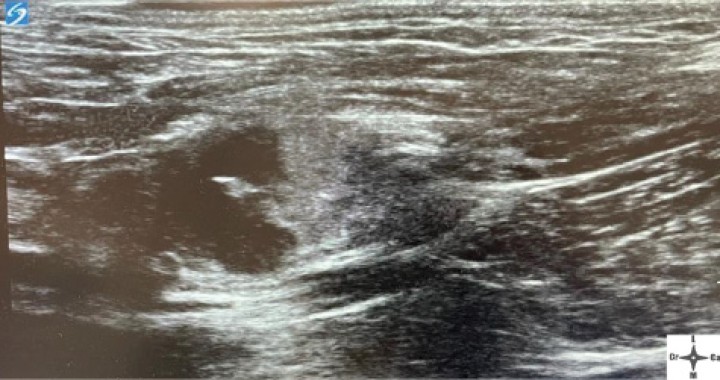

<p>Ventana acústica observando la neoplasia cavitada previamente a la inyección del anestésico local con contraste iodado.</p>

Ventana acústica observando la neoplasia cavitada previamente a la inyección del anestésico local con contraste iodado.

Con el fin de evitar el uso de opioides, se planificó una ALO cuya premedicación consistió en dexmedetomidina (Dexmopet, Fatro, Barcelona) 8 µg/kg vía intramuscular, considerando el carácter nervioso y excitable del paciente. A los 15 minutos se canalizó la vena cefálica (Sterican 22G x 1, BBraun vetcare, Barcelona), previa preoxigenación, y la anestesia se indujo con 3,5 mg/kg de propofol intravenoso (IV) (Propofol Lipuro, BBraun Vetcare, Barcelona). El mantenimiento anestésico se realizó con sevoflurano (SevoFlo, Zoetis, Louvain-la-Neuve) (concentración de sevoflurano espirada entre 1,7-2,0) empleando una FiO2 de 0,5 y ventilación espontánea. Se monitorizó la pulsioximetría, temperatura, ECG, capnografía, presión arterial no invasiva (PANI) y espirometría mediante un monitor multiparamétrico (5S Datex-Ohmeda, Finlandia). Se planeó realizar una TC prequirúrgica para volver a valorar la masa antes de comenzar la cirugía. Aprovechando esta circunstancia, se colocó al paciente en decúbito lateral izquierdo, depilando la región cervical, y se procedió a realizar un bloqueo anestésico ecoguiado empleando un ecógrafo portátil (Sonosite M-turbo, Sonosite, EUA) con sonda lineal 10-15 MHz posicionada inmediatamente ventral al ala del atlas en sentido longitudinal a la columna cervical (Figs. 2 y 3). Se localizaron las raíces ventrales cervicales de C2 y C3, las cuales se visualizan en el plano interfascial entre los músculos omotransverso e intertransversos, como engrosamientos de este, siendo dichas raíces estructuras elipsoidales con un halo hiperecoico y su centro hipoecoico. La neoplasia se encontraba próxima al sitio de inyección (Fig. 4). Se realizó un abordaje en plano y se inyectó una mezcla de bupivacaína (Bupivacaine, BBraun, Barcelona) 0,5 % con contraste iodado (Ultravist 300, Berlimed S.A, Alcalá de Henares) en una proporción de 4:1, a razón de 0,15 ml/kg alrededor del espacio interfascial de C2, confirmando la hidrodisección de este plano (Fig. 4). Además, se realizó la inyección contralateral subcutánea en las ramas ventrales superficiales de C2, que se localizan anatómicamente aproximadamente entre 0,5 y 1 cm dorsal a la bifurcación de la vena yugular en la grasa subcutánea profunda al platisma, utilizando 0,1 ml/kg de bupivacaína 0,5 % (Fig. 5). Dichos bloqueos se realizaron tras un exhaustivo estudio de la anatomía de la región, el reconocimiento cadavérico de dichas estructuras y empleando como referencia tanto el bloqueo descrito en equinos como el bloqueo intermedio del plexo cervical descrito en humanos. Se utilizó una aguja espinal (Spinocan Quincke 22 gauge, BBraun, Barcelona). Una vez realizado el bloqueo se repitió inmediatamente otra TC para evaluar la distribución de la solución inyectada (Figs. 6 y 7).